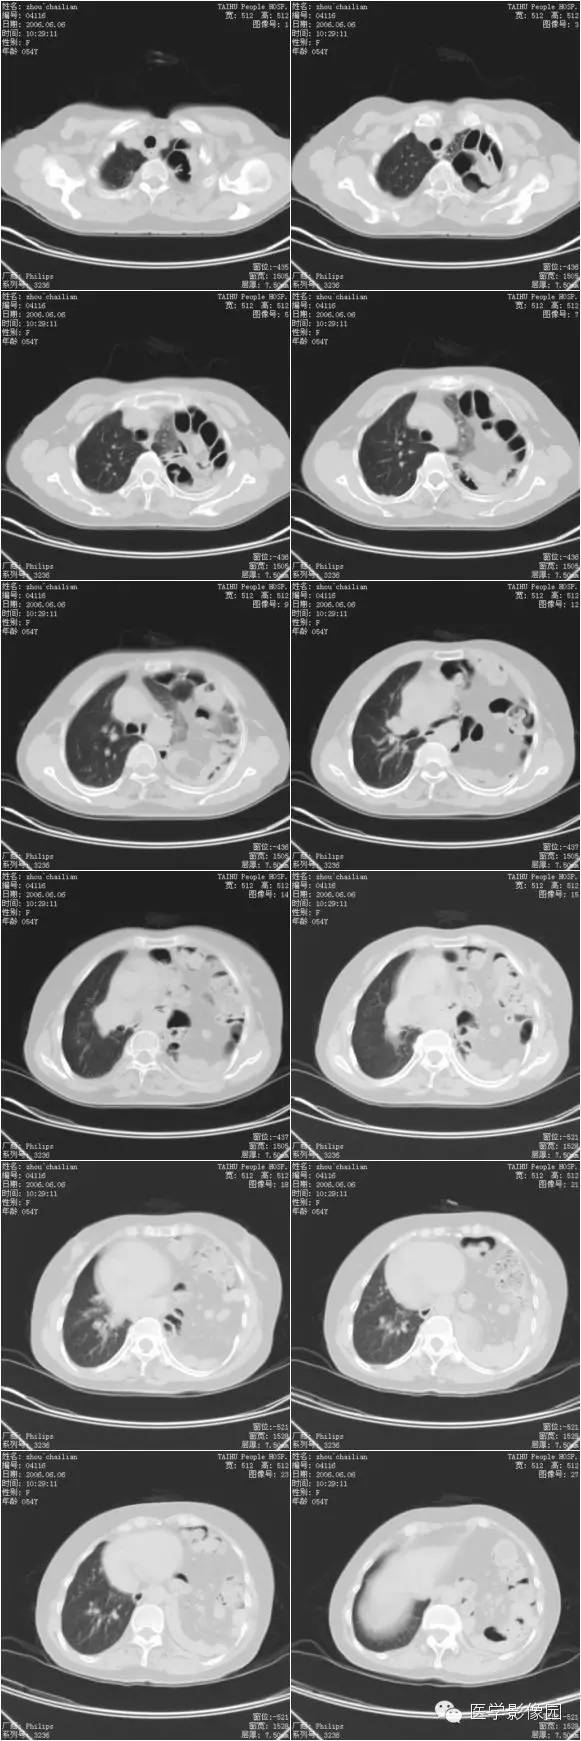

膈疝1例X线及CT影像表现

膈疝的形成除先天性膈肌融合部缺损和薄弱点外,还与下列因素有关:

①胸腹腔内的压力差异和腹内脏器的活动度;各种引起腹内压力增高的因素如弯腰、排便困难和怀孕等均可促使腹内脏器经膈肌缺损和薄弱部进入胸内。

②随着年龄增长,膈肌肌张力减退和食管韧带松弛,使食管裂孔扩大,贲站或胃体可以经过扩大的食管裂孔突入后纵隔。

③胸部外伤尤其胸腹联合伤引起膈肌破裂。